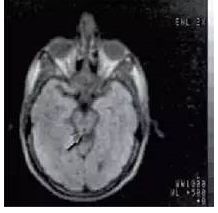

首次头颅 CT 检查

0.15T磁体。1980年12月3号得到了第一幅

人类头部核磁共振图像后来,在优化了

序列设计后,他们又获得了体部图像

放射科医生也第一次看到了可分辨的器官

丁汉的橙子和首次头颅 MR 成像